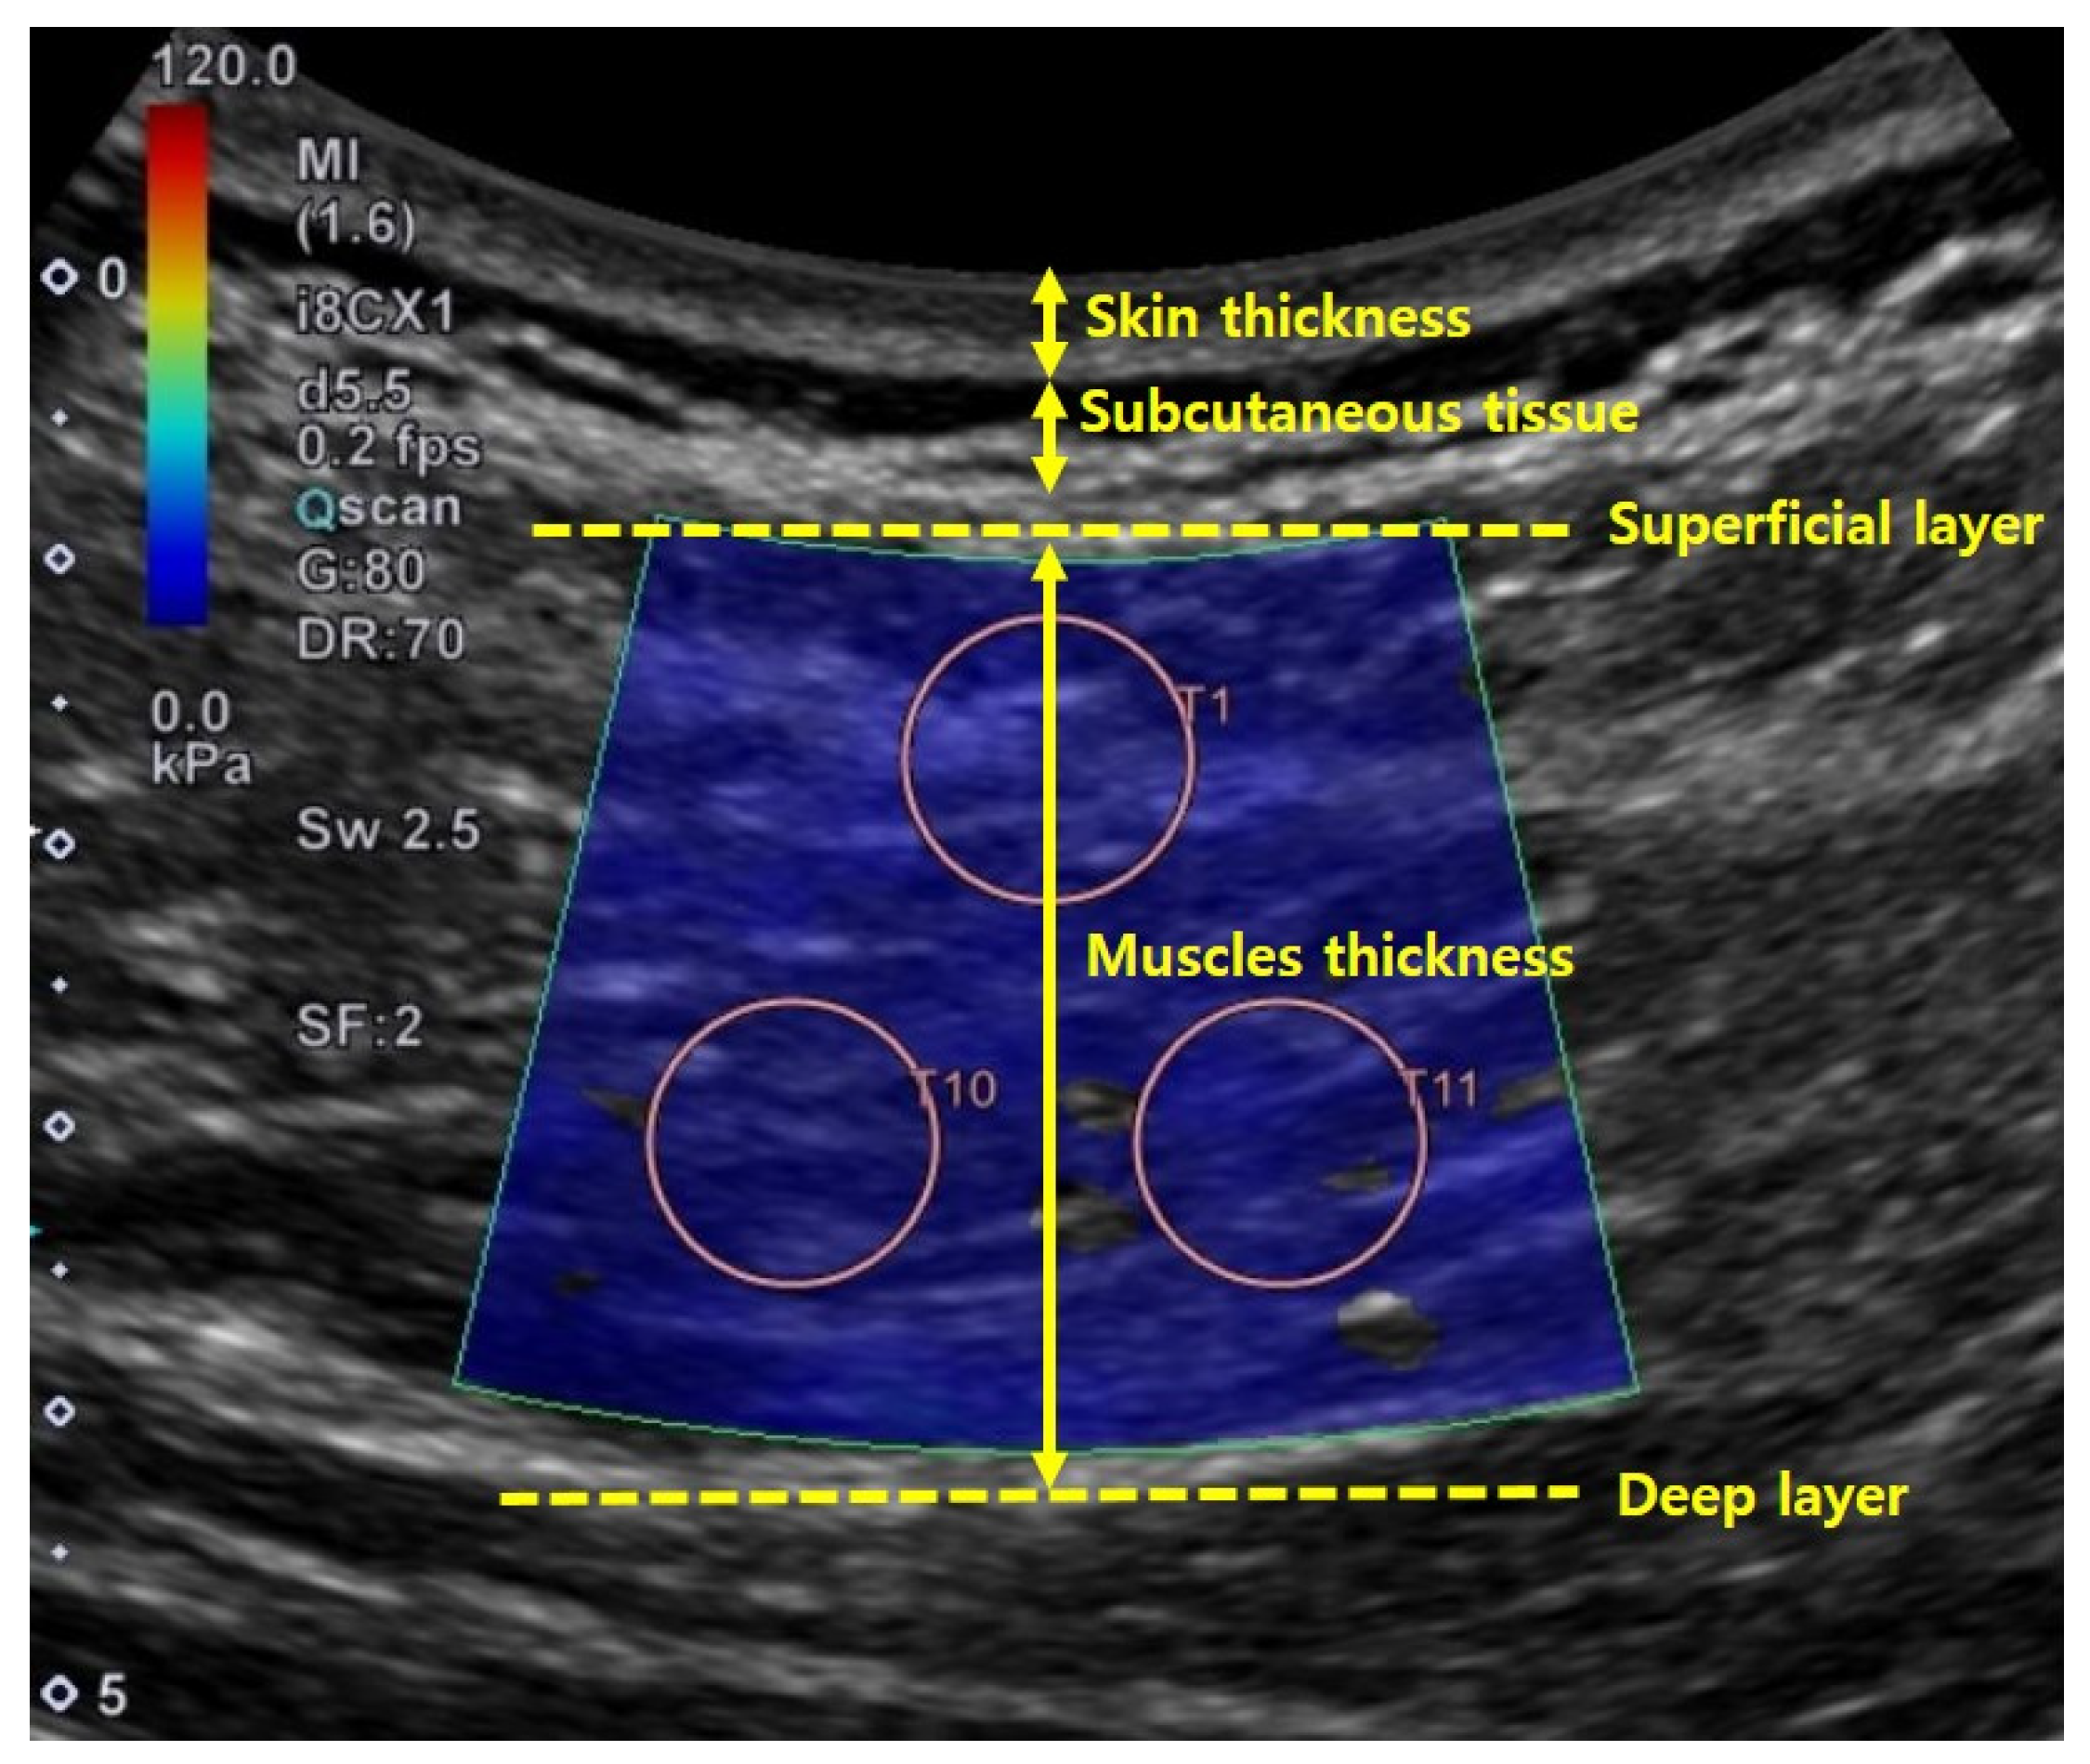

2.3. Ultrasound Measurement

3.2. Skin and Muscle Thickness